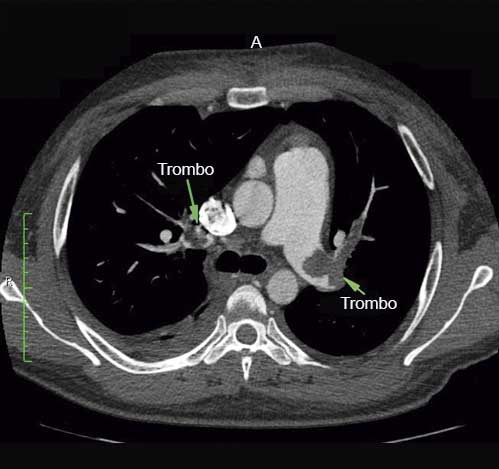

En la angiotomografía pulmonar de control realizada a los 8 días, se observó persistencia de imagen de trombo en la rama proximal de la arteria pulmonar izquierda y derecha (figura 5).

Angiotomografía cardiaca posterior a la terapia fibrinolítica. Persistencia de imagen de trombo en ambas arterias pulmonares